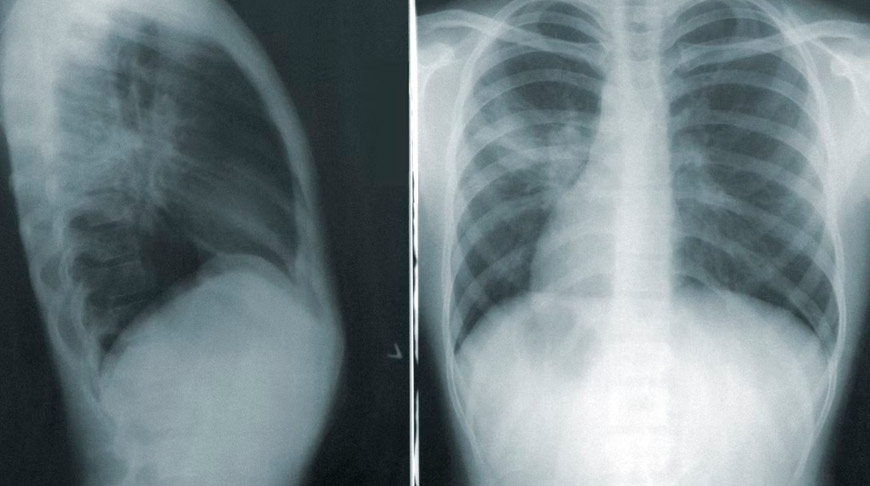

Причина внебольничной пневмонии - пневмококк. Врач назвал и симптомы болезни: кашель с мокротой, температура выше 38°С и лейкоцитоз. Пациентам, у которых есть подозрение на внебольничную пневмонию, рекомендована обзорная рентгенография органов грудной полости в передней прямой и боковой проекциях. По статистике, 53% приходится на нижнюю проекцию правого легкого, 43% - на нижнюю долю левого легкого.